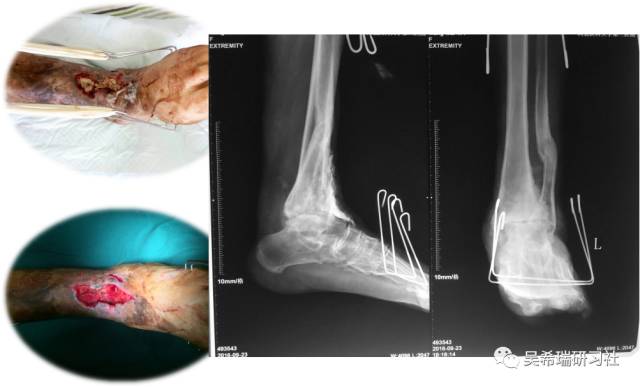

男  43岁 从2米处摔伤  开放性Pilon骨折

TIPS:关节内骨折非跨越关节固定技术一期应用骨水泥 + 开放植骨技术腓骨克氏针固定技术截骨矫形胫骨近端取骨技术